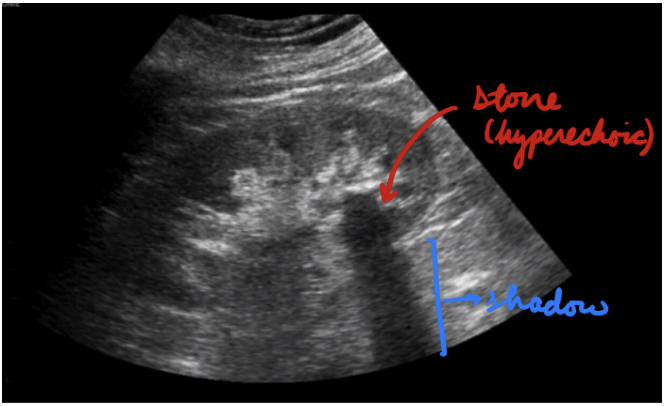

Nephrolithiasis: Ultrasound

Minimize radiation exposure (pregnant, pediatric)

Hyperechoic stones + Shadowing